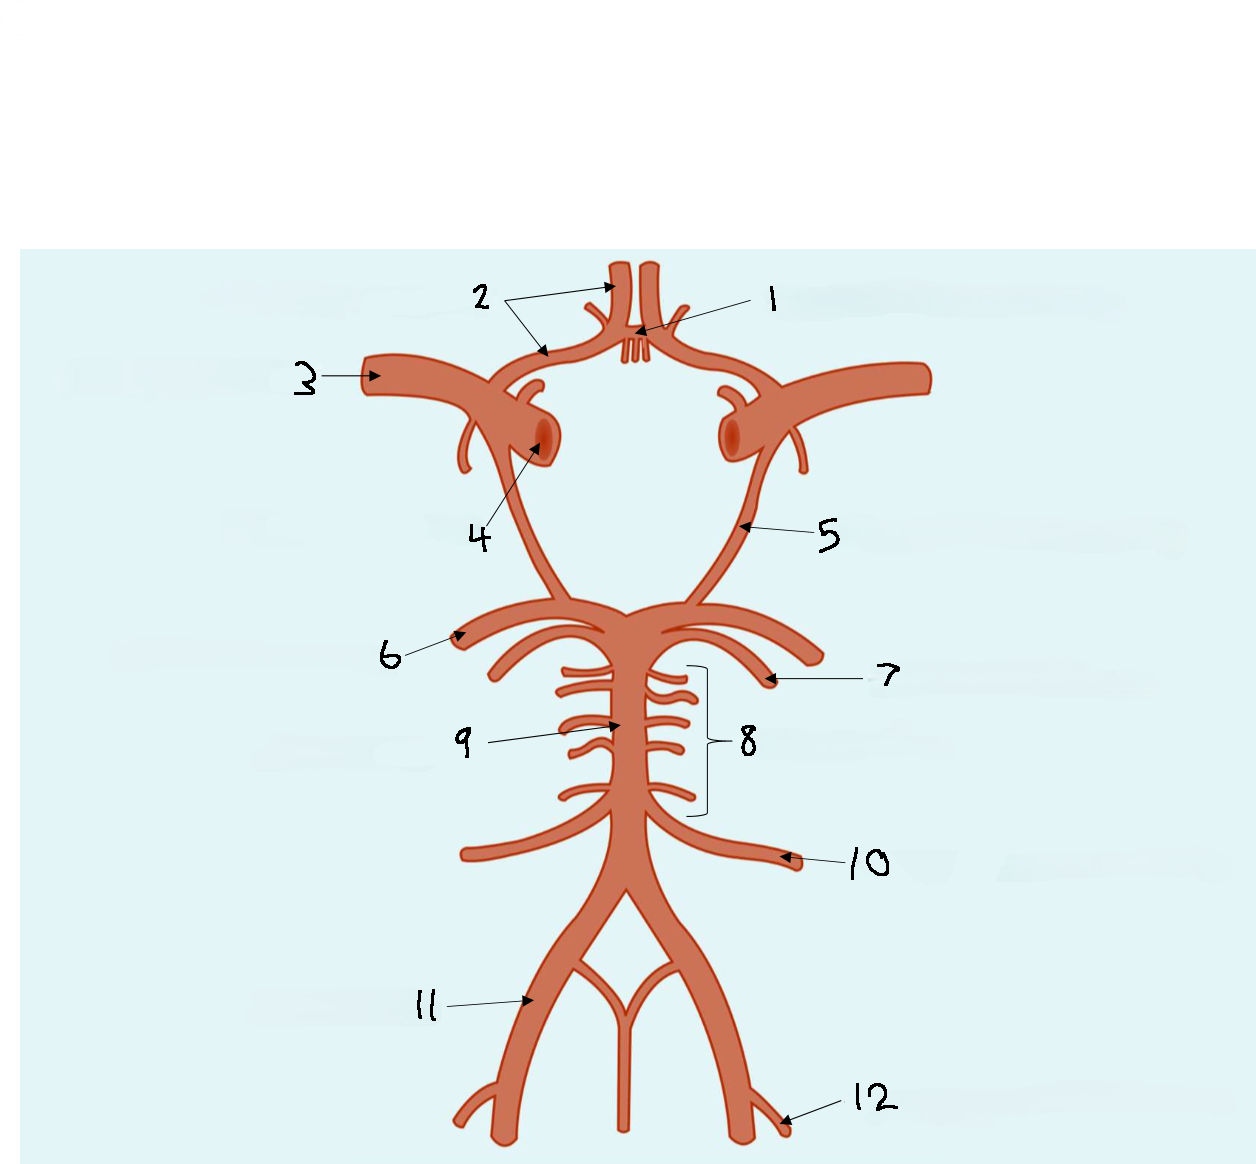

What is 1?

anterior communicating artery

What is 2?

anterior cerebral artery

What is 3?

middle cerebral artery

What is 4?

internal carotid artery

What is 5?

posterior communicating artery

What is 6?

posterior cerebral artery

What is 7?

superior cerebellar artery

What is 8?

pontine arteries

What is 9?

basilar artery

What is 10?

anterior inferior cerebellar artery

What is 11?

vertebral artery

What is 12?

posterior inferior cerebellar artery